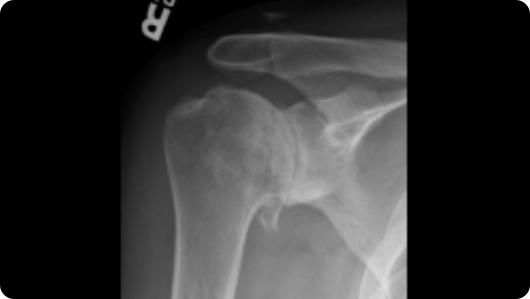

Radiographic image of shoulder arthritis Radiographic image of a total shoulder replacement

Shoulder Arthritis